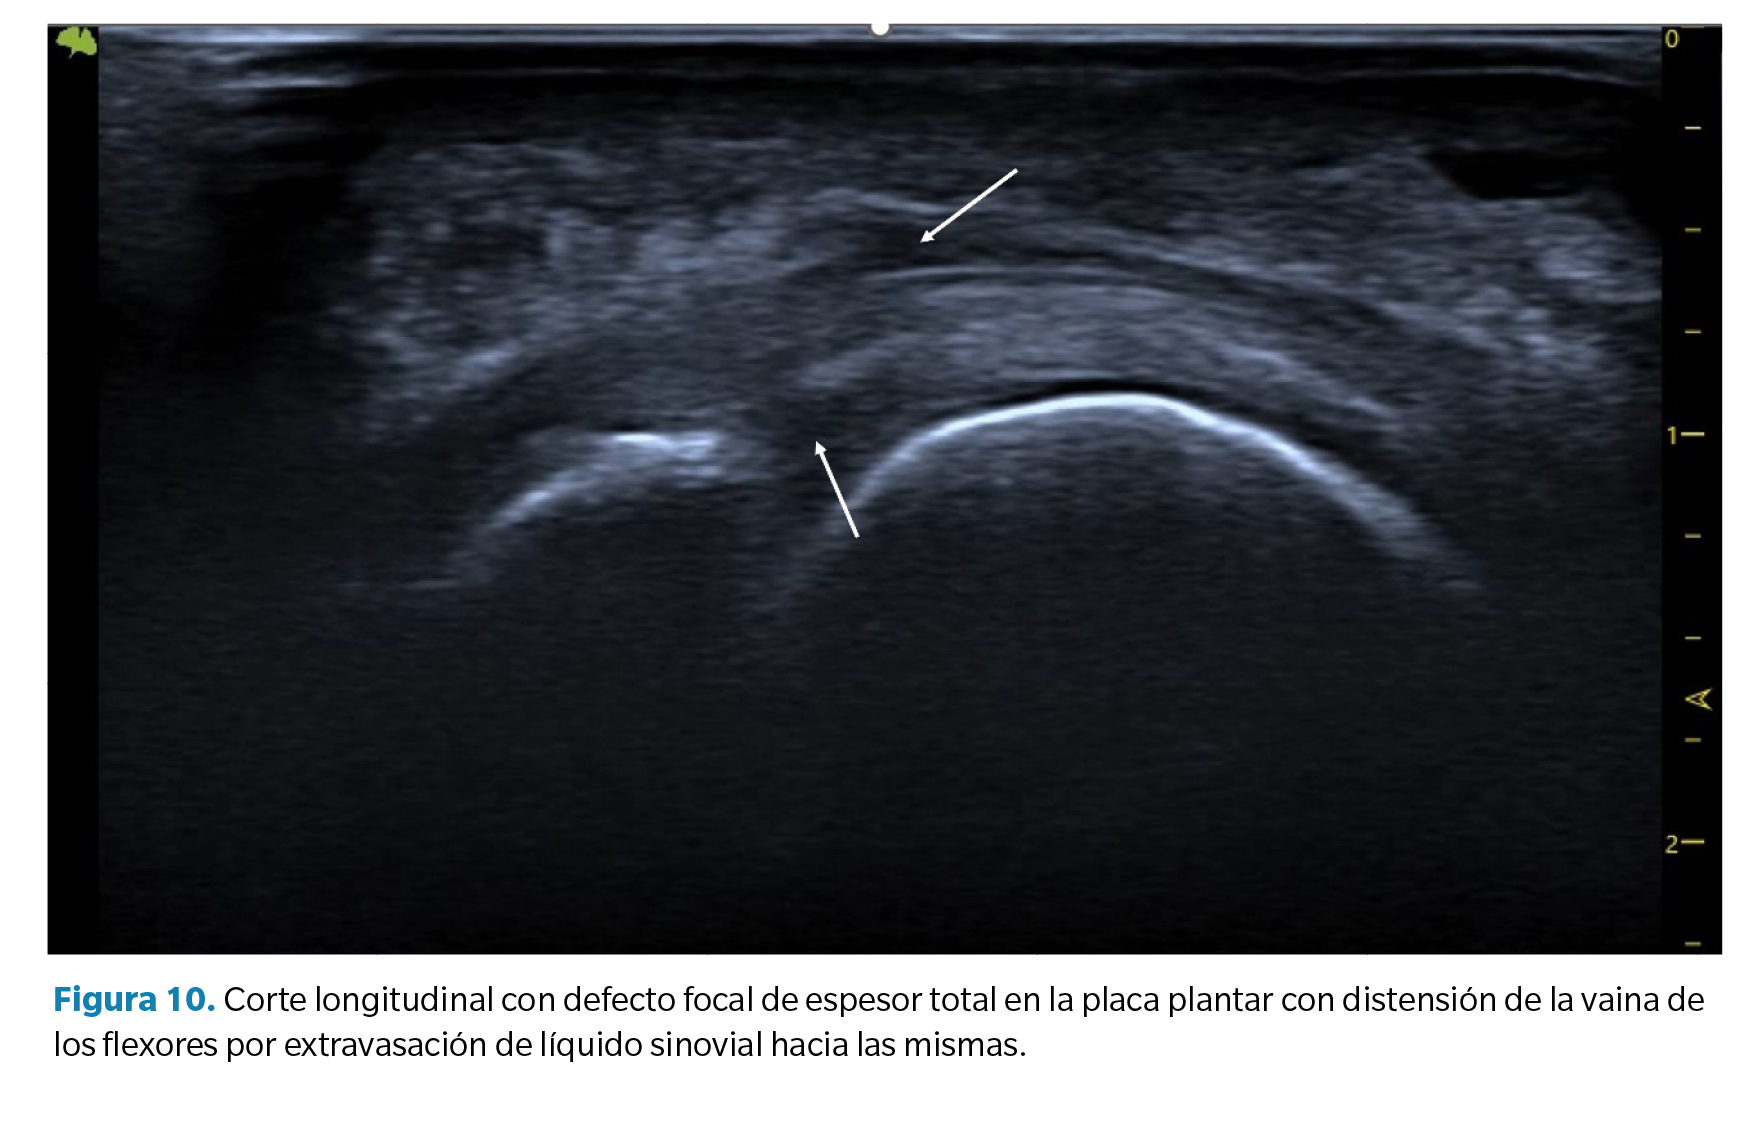

1. Líquido articular (sinovitis) plantar o dorsal. Derrame sinovial. Como la placa plantar constituye el cierre plantar de la cápsula articular, los desgarros de la placa pueden dar lugar a un aumento significativo del líquido sinovial que se manifiesta como un derrame sinovial apreciable a nivel dorsal y a nivel plantar. En algunos casos este líquido puede filtrarse hacia los tendones flexores manifestando un halo hipoecoico en los mismos que se asemeja a la imagen característica de una tenosinovitis con distensión de la vaina tendinosa (Figura 10).